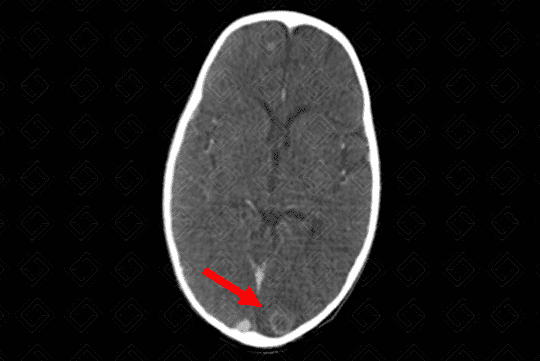

Texto alternativo para a imagem Figura 1. Créditos: Dra Elazir Mota - Rio de Janeiro/RJ

Descrição da lesão (figuras 1 e 2): Abcesso cerebral (tuberculoma). Tomografia computadorizada do crânio com contraste venoso: lesão ovalada, bem definida, hipodensa, com realce periférico pelo meio de contraste (captação anelar) e discreto edema de permeio à lesão, na região occipital esquerda.